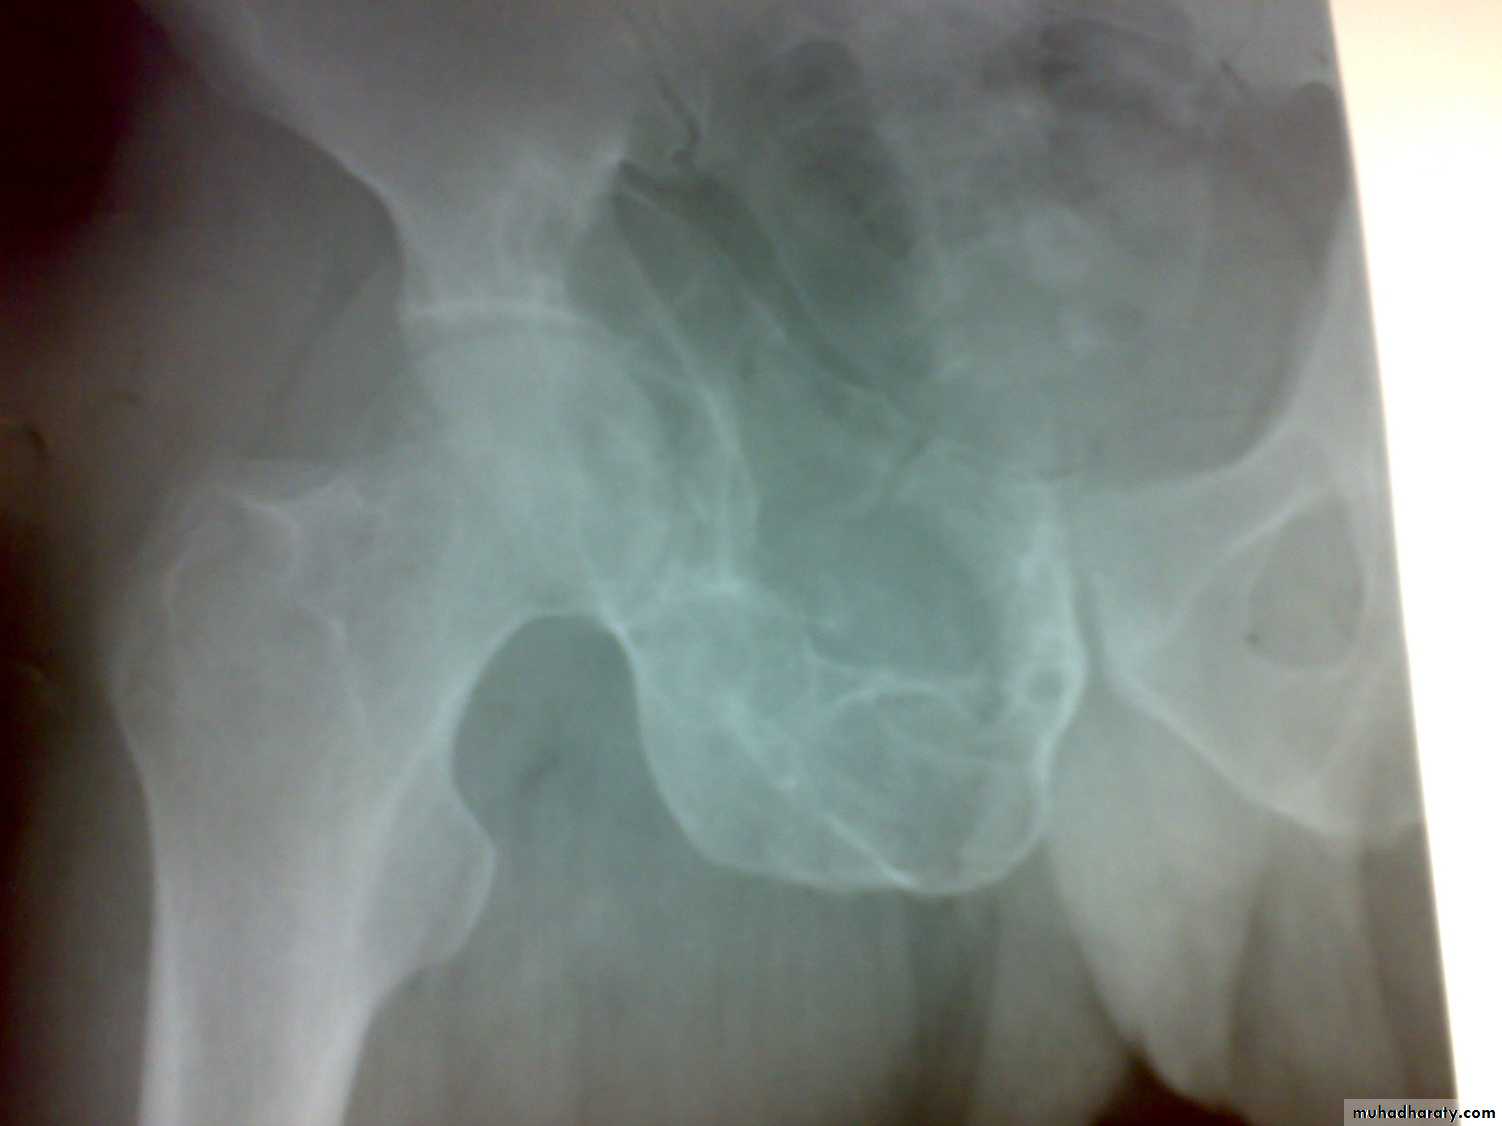

There is predilection to vertebral bodies ( 50%), and the large synovial joints ( hip ,knee, less often shoulder or ankle).

These changes affected either the synovium (SYNOVITIS) or the bone (OSTITIS) is affected and then spread to the near by structure and whole joint affected ( ARTHRITIS).

Radiological features

early changes:

Soft tissue swelling, Periarticular osteoporosis

Loclized osteoprosis (Bone ends ‘washed – out’ or localized decalcification ).

Narrowing and irregularity of the articular ends.

Late changes:

Erosions of the subarticular cartilage.

cystic changes appeared.